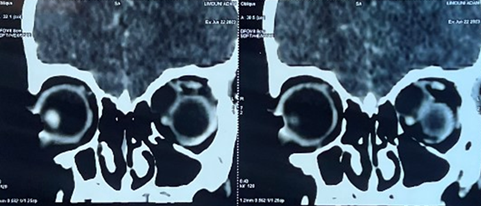

The craniofacial ct-scan (figure 2)

showed grade 3 exophthalmos with a thickening and infiltration of the left

palpebral soft tissues, with evidence of a medial extra conical collection of

mild density, measuring 31 x 22 mm and extending over 21 mm, with a mass effect

on the superior rectus muscle, which was tumefied and compressed. It also had a

mass effect on the ipsilateral optic nerve, which was discreetly swollen

Figure 2. Coronal ct scan images showing the

hypodense mass and its effect on the globe